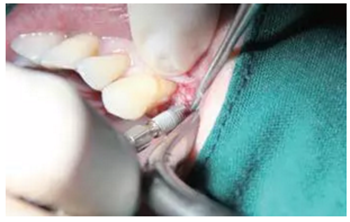

備孔

戴上導(dǎo)板逐級備孔注意導(dǎo)板的就位要準(zhǔn)確不晃動,備孔時(shí)應(yīng)通過充分的提拉鉆頭來獲得良好的冷卻。

圖3 戴上導(dǎo)板并按照操作說明書逐級備孔